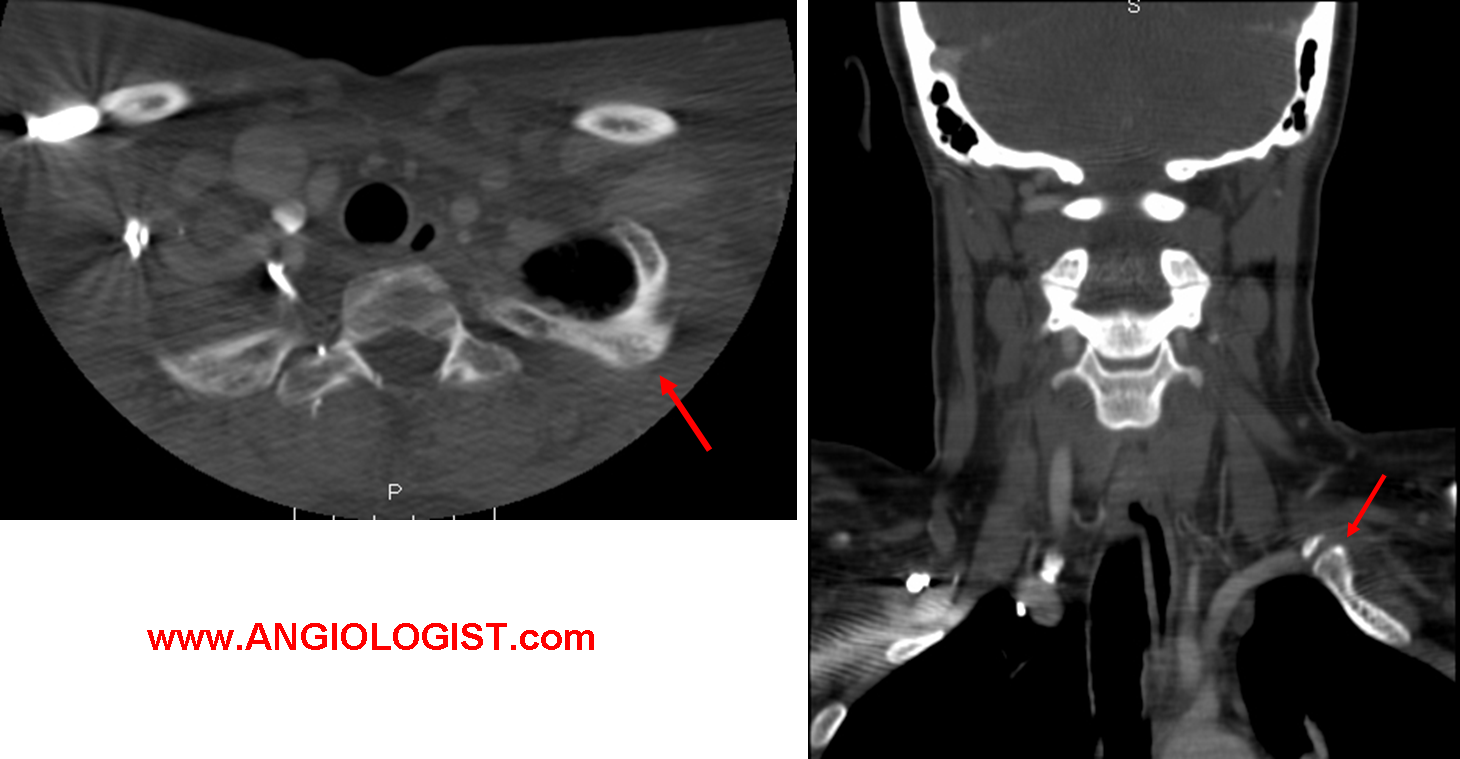

- Arterial TOS manifests as emboli that are showered distally from the area of compression. A common mechanism is repeated injury. In sports this is typical of overhead pitchers. Most often a digit or the whole hand are affected, with more proximal symptoms possible, but less common. Thus, arterial thoracic outlet syndrome is different than the other types in that symptoms are more distal, while neck pain and scalene muscle tenderness are absent. Imaging such as duplex ultrasound or CT angiography can often demonstrate the focal arterial flaws that are the source of the emboli (such as aneurysm formation).